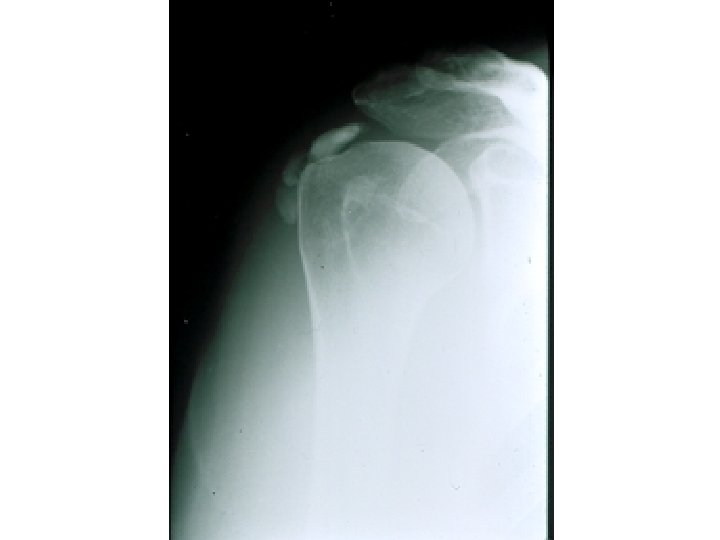

SEMIOLOGIE DE L’EPAULE IV – DIAGNOSTIC ETIOLOGIQUE A – Atteintes périarticulaires (l’ancienne P. S.

SEMIOLOGIE DE L’EPAULE IV – DIAGNOSTIC ETIOLOGIQUE A – Atteintes périarticulaires (l’ancienne P. S. H) 80% 1° Tendinites 2° Epaule douloureuse hyperalgique 3° Epaule douloureuse mixte

SEMIOLOGIE DE L’EPAULE IV – DIAGNOSTIC ETIOLOGIQUE A – Atteintes périarticulaires B – Rétraction

SEMIOLOGIE DE L’EPAULE IV – DIAGNOSTIC ETIOLOGIQUE A – Atteintes périarticulaires B – Rétraction capsulaire de l’épaule (épaule gelée – algodystrophie) C – Arthroses de l’épaule D – Arthrites – rhumatismale (contexte) – infectieuse +++